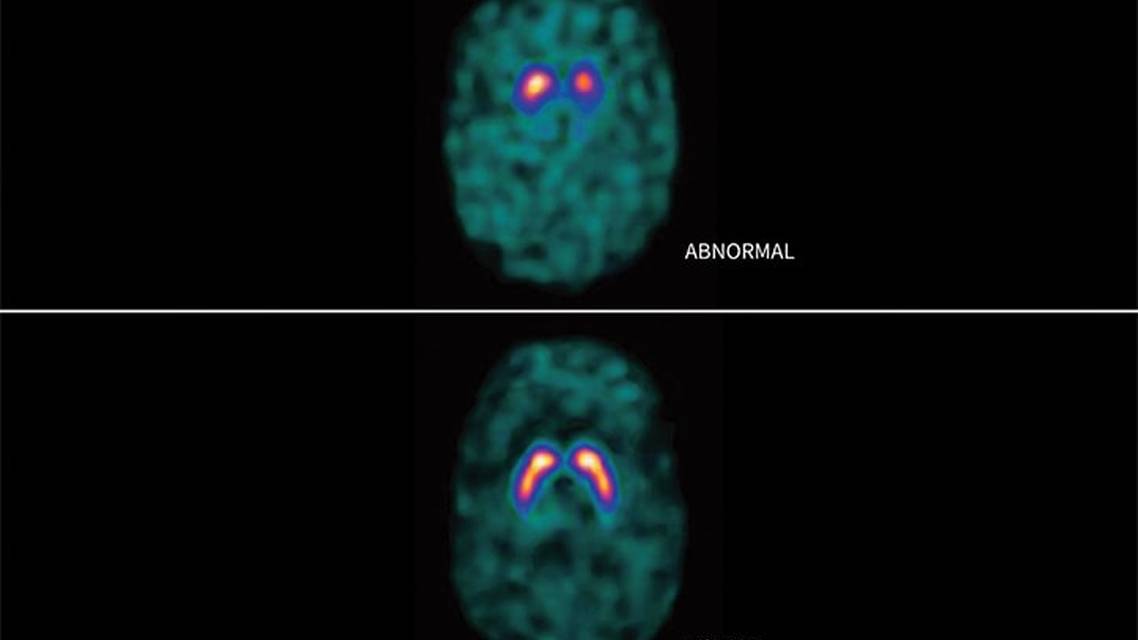

The majority of DaTscan results are interpreted qualitatively and provide a visual indication of the number of dopamine-secreting cells. In a positive scan, loss of the usual comma-shaped pattern of radiotracer uptake in the striatum is indicative of reduced DAT binding, consistent with the dopaminergic deficit seen in neurodegenerative parkinsonism (Figure).

DaTscan images demonstrate presynaptic dopaminergic innervation, distinguishing people with PD or other forms of neurodegenerative parkinsonism from those with essential tremor (ET), those with drug-induced parkinsonism, or unaffected individuals.3 Because atypical parkinsonism also results in a presynaptic dopaminergic deficit, DaTscan images cannot differentiate PD from atypical parkinsonism (ie, multiple system atrophy [MSA], progressive supranuclear palsy [PSP], corticobasal degeneration [CBD]).4 DaTscan results may be abnormal in patients with idiopathic normal pressure hydrocephalus, and these results have been shown to normalize after shunting, suggesting reversible striatal dysfunction.5 In rare cases, a DaTscan may have normal results in a person with parkinsonian symptoms meeting diagnostic criteria for PD, which is known as a scan without evidence of dopamine deficit (SWEDD).